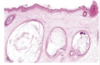

Vesicle / Bulla

Palpable elevation filled with clear fluid

Vesicle - < 1cm

Bulla - > 1cm